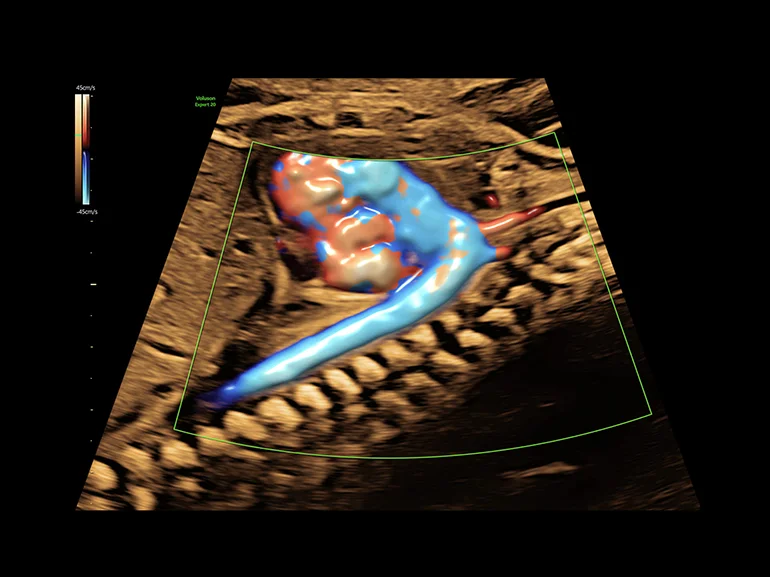

Дуга аорты плода (26 недель), технология Radiantflow

Трехмерный режим — дальнейшее развитие В-режима. Объемное трехмерное изображение достигается путем компьютерного преобразования сигнала, полученного при помощи датчика с изменяющейся плоскостью излучения. Данный метод позволяет получить объемное изображение органа и исследовать его в различных проекциях. Особенно информативным он оказался в пренатальной диагностике врожденных аномалий развития плода. В ультразвуковых приборах экспертного и высокого классов имеется режим трехмерной энергетической доплерографии или трехмерной ультразвуковой ангиографии. Прибором реконструируется трехмерное изображение только цветовой части эхограммы, характеризующей кровоток в сосудах. Меняя ракурс наблюдения, поворачивая трехмерное изображение сосудов, получают представление о пространственном расположении и форме сосудов, что дает дополнительную диагностическую информацию.